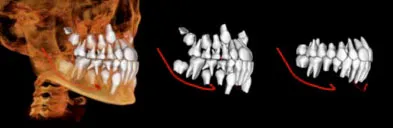

This type of imaging allows us to obtain highly accurate information, in an office setting, that was never before thought to be possible. These 3-D radiographic images can obtain very pertinent information on the entire head and neck region. This allows for better diagnosis, better treatment planning, which in turn leads to better surgery. Undistorted, anatomically correct views of the jaws, teeth and facial bones are easily generated. Three-dimensional images enable a level of anatomical accuracy and patient care not possible with 2-D technologies.

Before

After